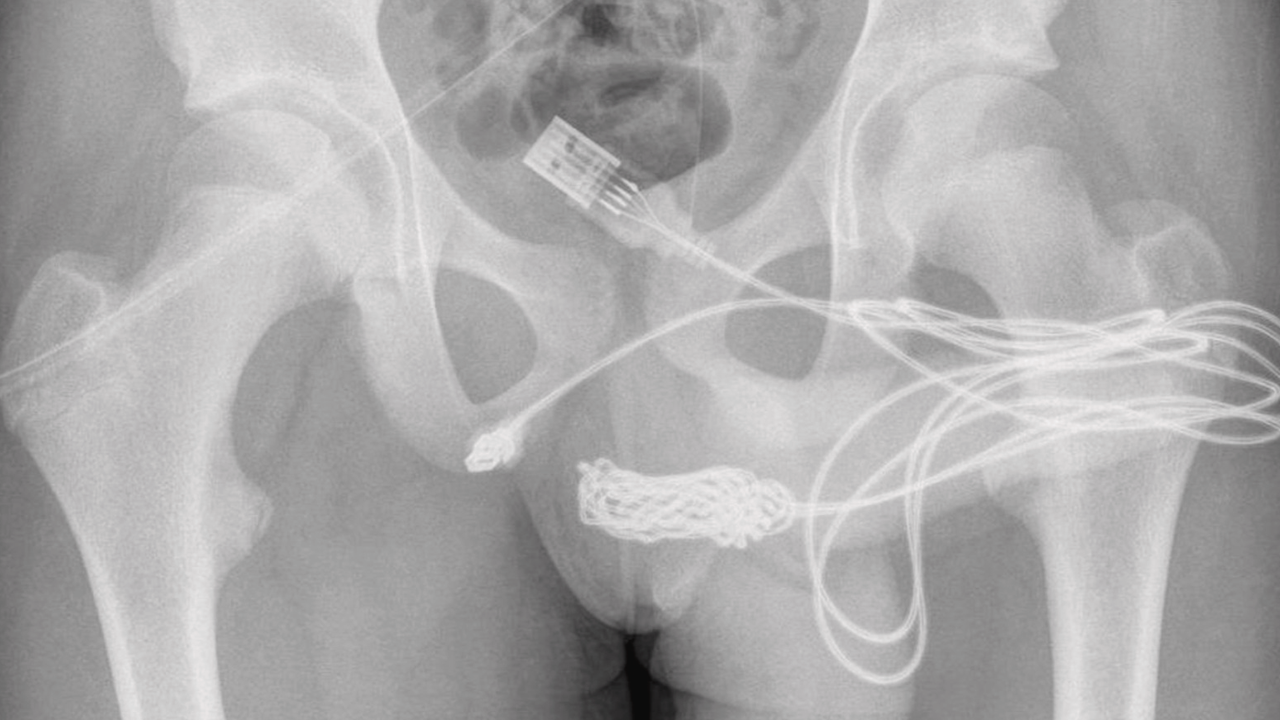

"The two distal ports of the USB wire were found to be protruding from the external urethral meatus whilst the middle part of the knotted wire remained within the urethra," doctors noted.

When attempts to remove the cable with a metal rod didn't work, the boy had to go into surgery where surgeons made an incision between his genitals and anus to get the cable out, which thankfully went successfully.